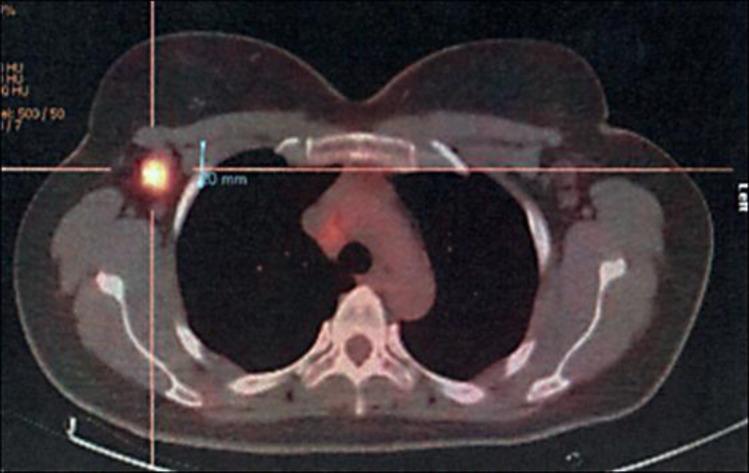

A 42-year-old, premenopausal woman presented with facial paralysis on the central left side accompanied by a left tongue deviation, an upward vertical nystagmus, moderate spastic paraparesis, dystonic posturing of the left foot, lower limb hyperreflexia and bilateral extensor plantar reflex. After ruling out all other potential neurologic causes, PNS was suspected but no ONAs were found. A PET-CT scan detected increased metabolism in the right breast, as well as an ipsilateral thoracic interpectoral adenopathy. Core biopsy confirmed the presence of an infiltrating duct carcinoma. After breast surgery, the neurologic symptoms disappeared. One week later, the patient was readmitted to the hospital with a bilateral fatigable eyelid ptosis, and two weeks later, there was a noticeable improvement in eyelid ptosis, accompanied by a rapid and progressive development of lower spastic paraparesis. She started adjuvant treatment with chemotherapy with marked clinical and neurological improvement, and by the end of radiotherapy, there were no signs of neurologic impairment.

一名42岁的绝经前女性出现左侧中枢性面瘫,伴有左侧舌偏斜、向上垂直性眼球震颤、中度痉挛性截瘫、左脚肌张力障碍姿势、下肢反射亢进和双侧巴宾斯基征阳性。排除所有其他潜在的神经病因后,怀疑为PNS,但未发现ONA。PET-CT扫描显示右乳代谢增加,同侧胸肌间淋巴结肿大。芯针活检证实存在浸润性导管癌。乳腺手术后,神经症状消失。一周后,患者因双侧可疲劳性眼睑下垂再次入院,两周后,眼睑下垂有明显改善,同时下半身痉挛性截瘫迅速进展。她开始接受辅助化疗,临床和神经症状均有明显改善,放疗结束时,无神经功能损害迹象。